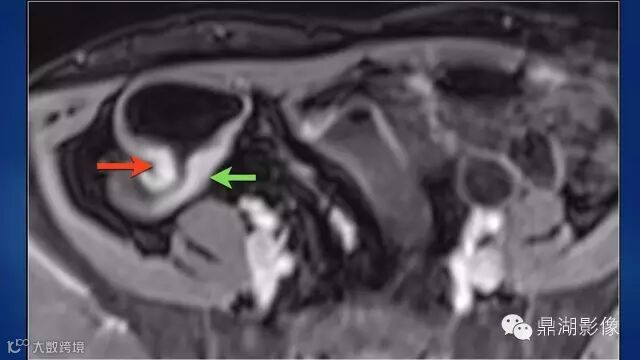

do you know comb sign?

The comb sign refers to the hypervascular appearance of the mesentery in active Crohn disease.

Very impressive image